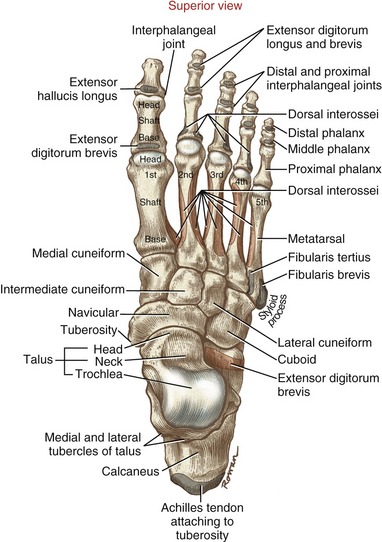

Osteology & Attachments

• Superior view

Columns

• Medial

• 1st metatarsal

• medial cuneiform

• navicular

• talus

• Middle

• 2nd + 3rd metatarsals

• middle + lateral cuneiforms

• Lateral

• 4th + 5th metatarsals

• cuboid

• calcaneus